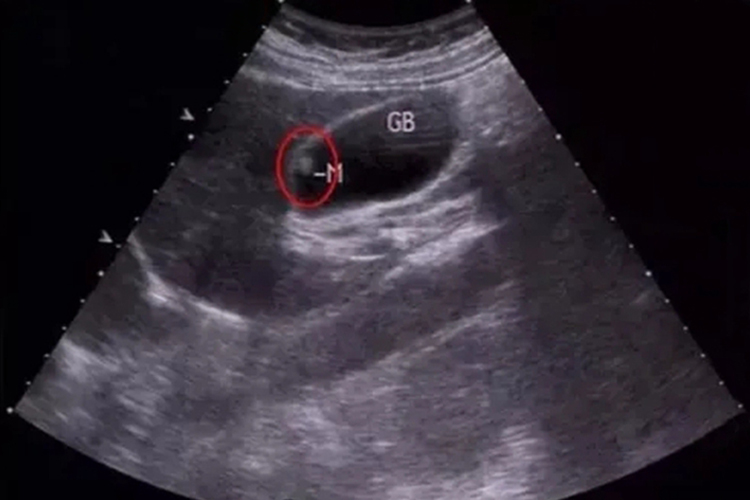

胆固醇息肉外观黄色分叶状、桑葚样、柔软易脱落,炎症性息肉有蒂,蒂粗或不明显,颜色与邻近黏膜相似或稍红。B超表现为胆囊壁小结节状或乳头状隆起,无声影,且不随体位改变而移动。